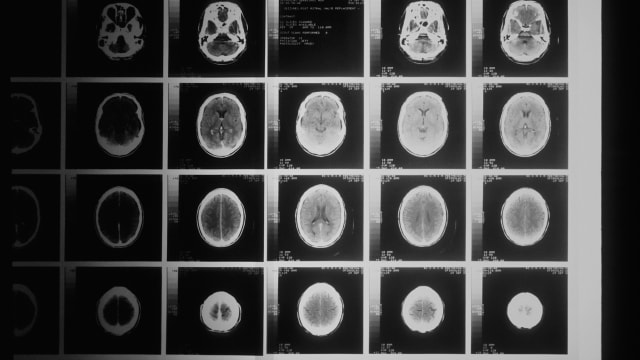

Der Impfstoff verzögert das Wiederauftretens von Hirntumoren. | Unsplash

Die Teilnehmer erhalten vier Dosen über zwei Monate verteilt, gefolgt von einer Auffrischungsimpfung alle zwei Monate. Zusätzlich werden alle zwei Monate Gehirnscans durchgeführt, um Anzeichen einer Tumorprogression zu überwachen.